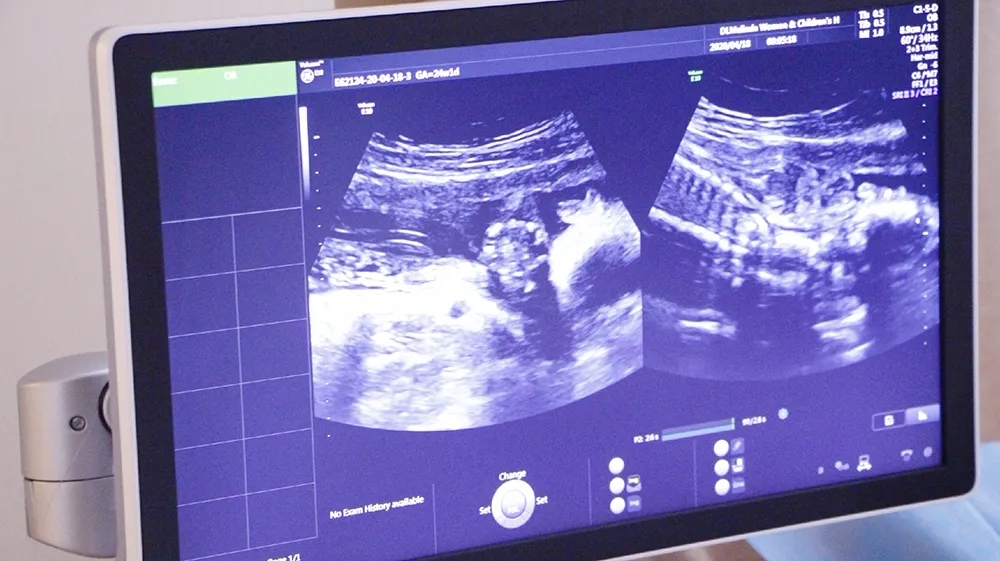

四维彩超是超声检查的一种,是孕期(zui)重要的一次超声检查,一般在孕24周进行,除了一般彩超的功能外,还可以进行胎儿头面部立体成像,可协助医生直接对胎儿先天畸形进行诊断,包括表面畸形、内脏畸形和头面部畸形,可实时观察胎儿动态的活动图像。

二维超声它是一个切面的成像,三维是在二维的基础上面提供一个立体的成像,而四维彩超就是在三维的基础上又加了一个时间的动态,多用于为胎儿拍照和录像以满足家长见到胎儿形象的愿望。

引进美国进口系列设备-清晰动态记录胎宝美琳达超声科引进多台美国GE-E10、美国GE-E8等系列机器。能够提高细节分辨率,实现在扫描同时即刻呈现胎儿标准生长曲线和相应测量数据。满足从早孕期研究到复杂胎心的全程早期检查和诊断,通过四维立体成像,清晰并动态记录宝宝在子宫内的活动和成长历程。

注重孕妈体验度-检查更舒适入院时,导医客服引领陪同检查,检查结果出来后专人电话通知。候诊时,大厅放置舒适的沙发可供休息,客服也会为客户提供饮品和食品等。检查时,四维彩超诊室设置适宜观看的高清电视屏幕,双屏互动模式,检查时孕妈可以清晰看见医生操作。检查床旁放置舒适纯皮沙发,支持家属陪伴检查。重要的是,美琳达也会提供胎儿写真照片,留作纪念。